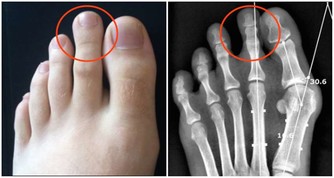

唇側紋:可能是胃病

皺紋始於嘴唇側邊緣,往下傾斜。右邊的皺紋透露出來的是肝臟和膽囊的負擔過重,左邊的皺紋則發出脾臟有問題的信號。嘴角有小皺紋則可能是是傲慢和有胃病的特徵。